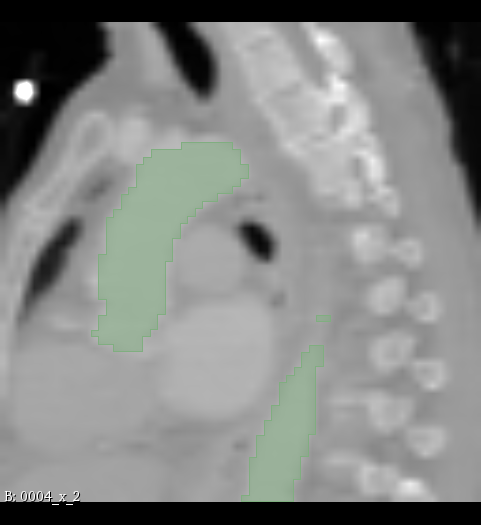

Figure 2: Illustration of the data from the TotalSegmentor data set [32] used in the experiments. The first row shows the axial, coronal and sagittal views passing the center of mass of the kidney in one of the data points. The second row shows the axial, coronal and sagittal views passing the center of mass of the aorta in one of the data points. The third row shows the axial, coronal and sagittal views passing the center of mass of the esophagus in one of the data points.

5.1 Data

The experiments are conducted with respect to the TotalSegmentor data set [32]. This data set contains 1204 CT images with 104 anatomical structures (27 organs, 59 bones, 10 muscles, 8 vessels). To illustrate the effect noise may have on organs with different shape, three different organs are chosen. This includes the right kidney which in general is pretty spherical, the aorta which is tubular and relatively thick and the esophagus which is tubular and relatively thin. For each of the organs, 400 cases is selected and split into 5 folds of 80 cases. Finally, the images are sub-sample to half resolution and patches of 643superscript64364^{3} voxels centered in each of the structures are extracted.